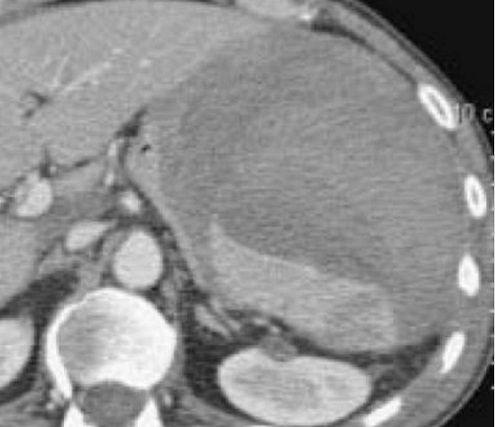

Image radiologique TDM d'un

traumatisme de la rate a grade IV avec aspect

radiologique de hematome itraparenchymeteuse marque

, dechirude capsulaire et de devascularisation de

bord anterieur . Coupe axiale TDM avec contrast

intraveineuse phase veineuse . |

Image rasdiologique d'une traumatisme de

la rate avec lesions hematome intraparenchymeteux

diffuse et dechirure de bord anterieure avec

devascularisation de artere splenique ( grade V ) .

Coupe TDM axiale phase veineuse |